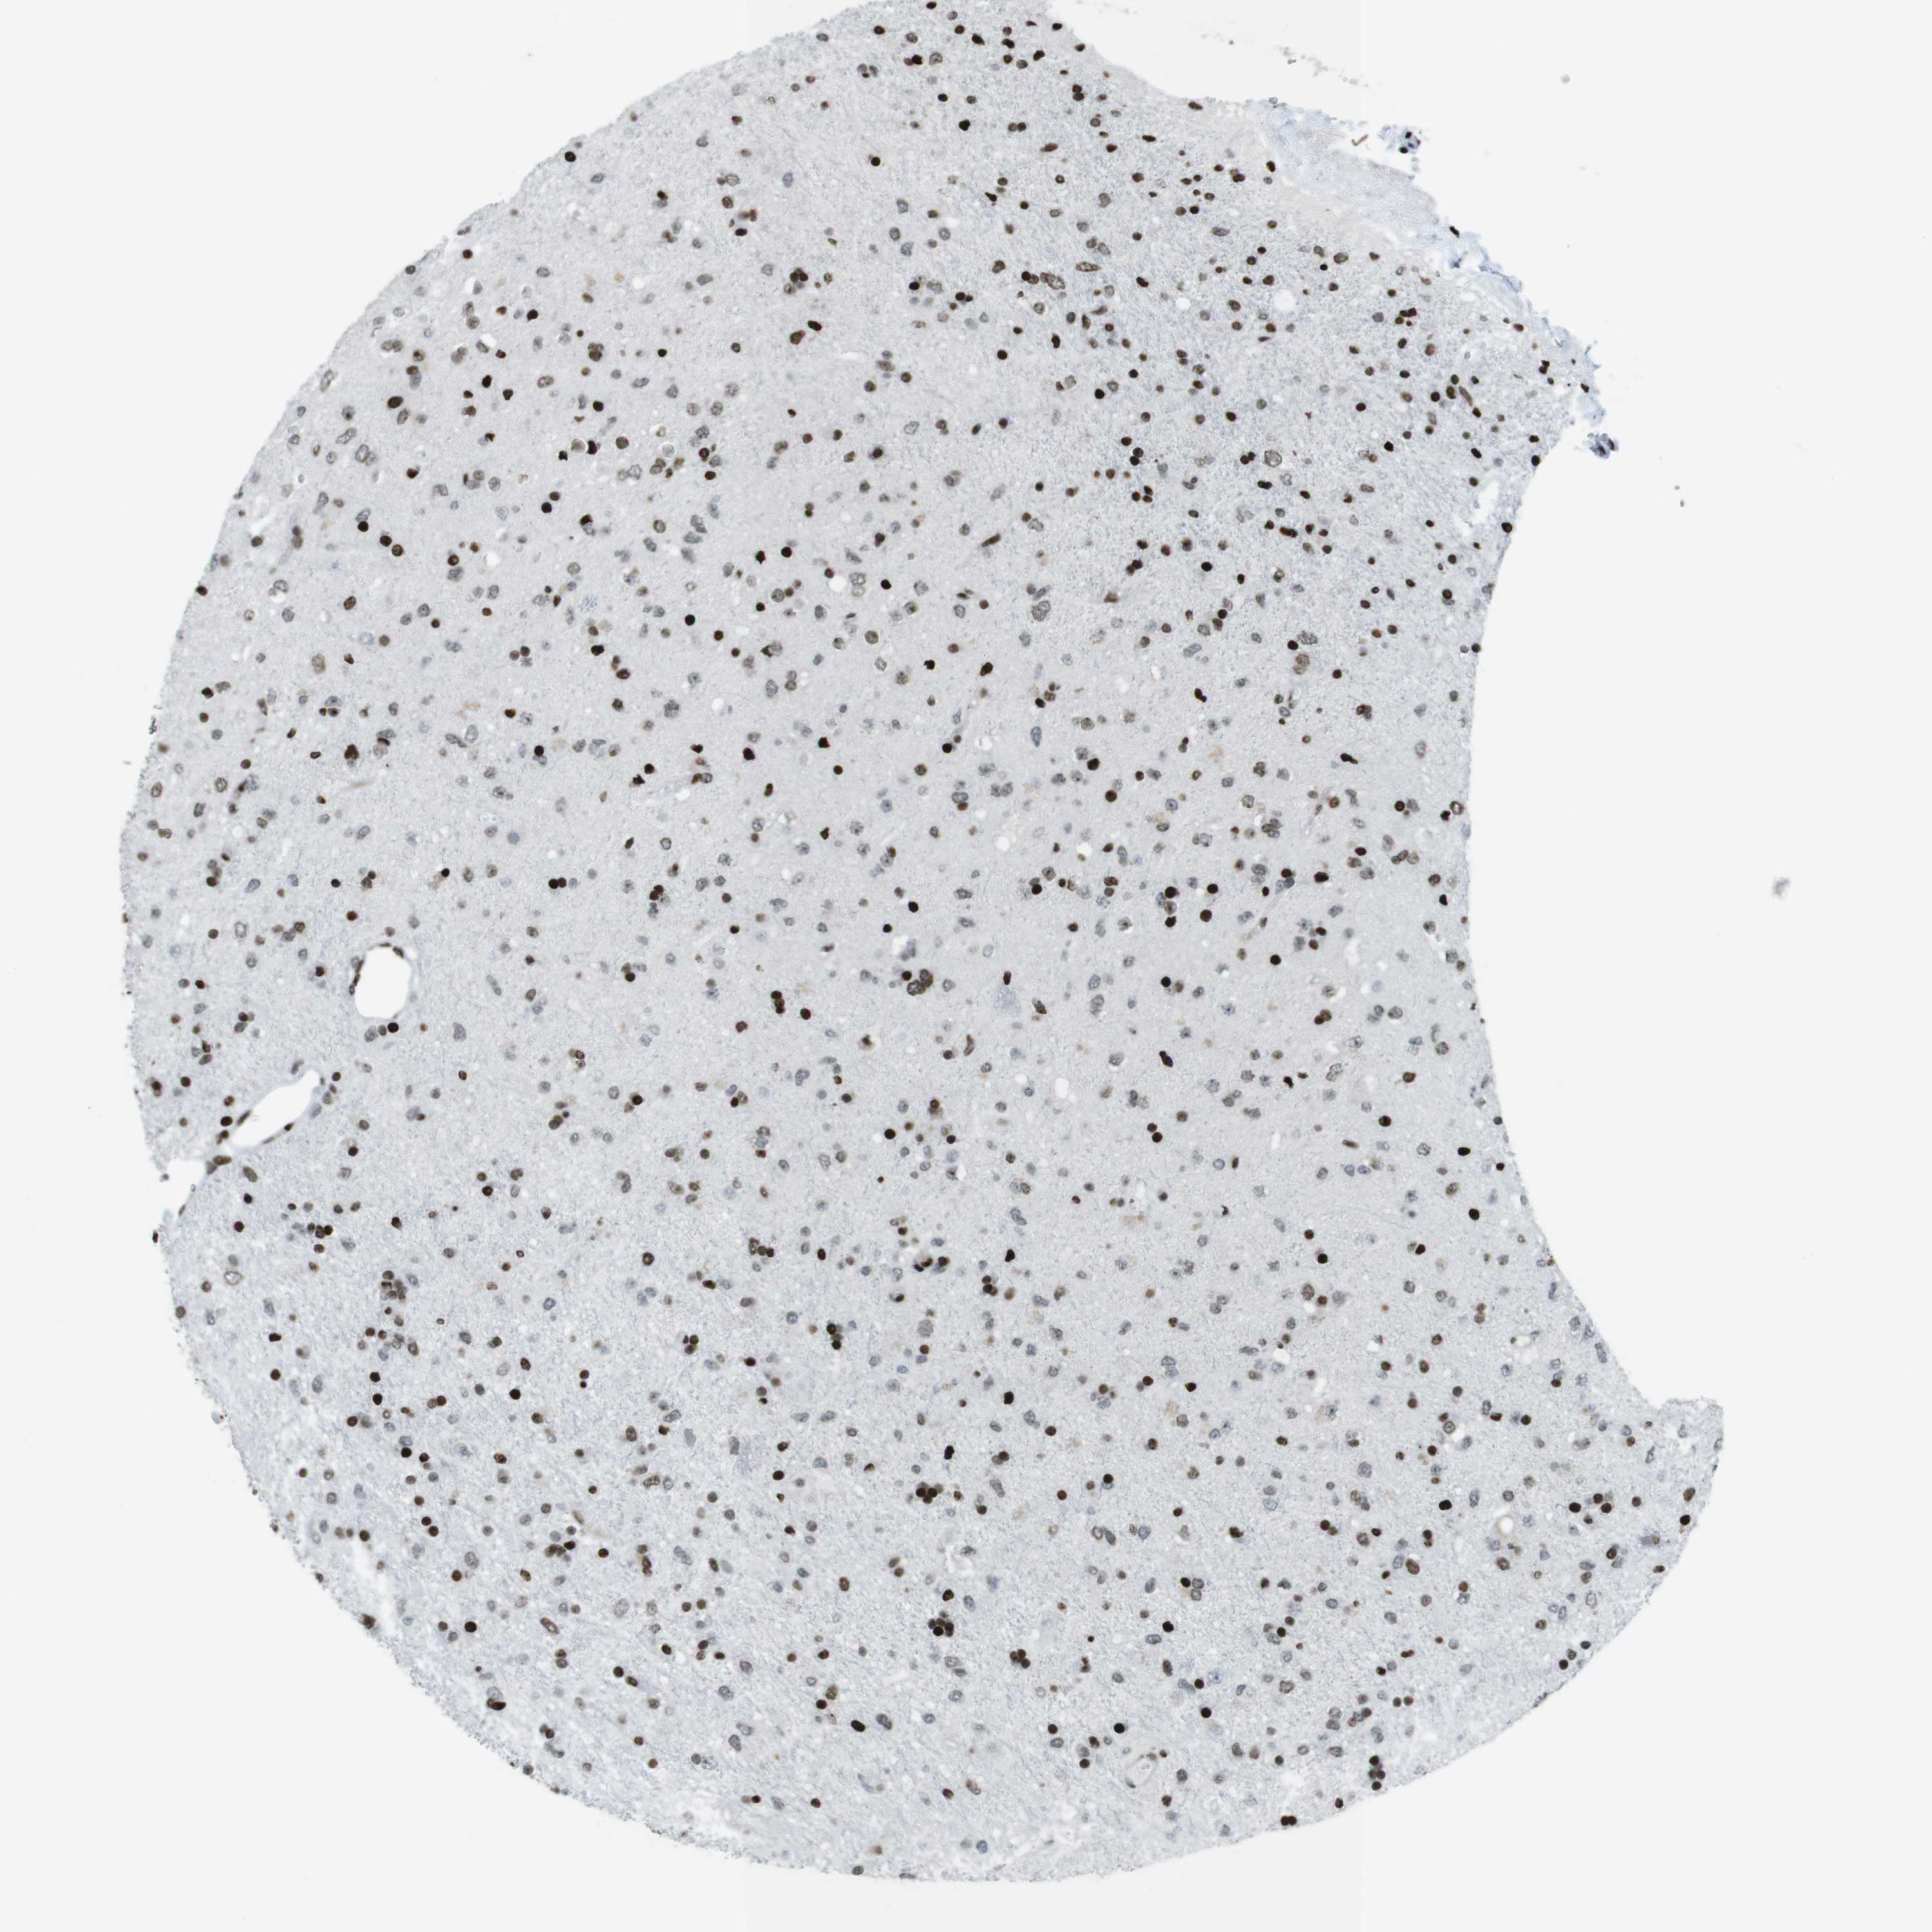

GLIOMA - Protein expressioni

A mouse-over function shows sample information and annotation data. Click on an image to view it in a full screen mode. Samples can be filtered based on level of antibody staining by selecting one or several of the following categories: high, medium, low and not detected. The assay and annotation is described here.

Note that samples used for immunohistochemistry by the Human Protein Atlas do not correspond to samples in the TCGA dataset.

Antibody stainingi

Antibody staining in the annotated cell types in the current human tissue is reported as not detected, low, medium, or high, based on conventional immunohistochemistry profiling in selected tissues. This score is based on the combination of the staining intensity and fraction of stained cells.

Each image is clickable and will lead to virtual microscopy that enables deeper exploration of all samples and also displays staining intensity scores, fraction scores and subcellular localization as well as patient and tissue information for each sample.

Antibody HPA041189

Antibody CAB012242

Staining

High

Medium

Low

Not detected

Intensity

Strong

Moderate

Weak

Negative

Quantity

>75%

75%-25%

<25%

None

Location

Nuclear

Cytoplasmic/membranous

Cytoplasmic/membranous,nuclear

Glioma, malignant, High grade

Glioma, malignant, Low grade